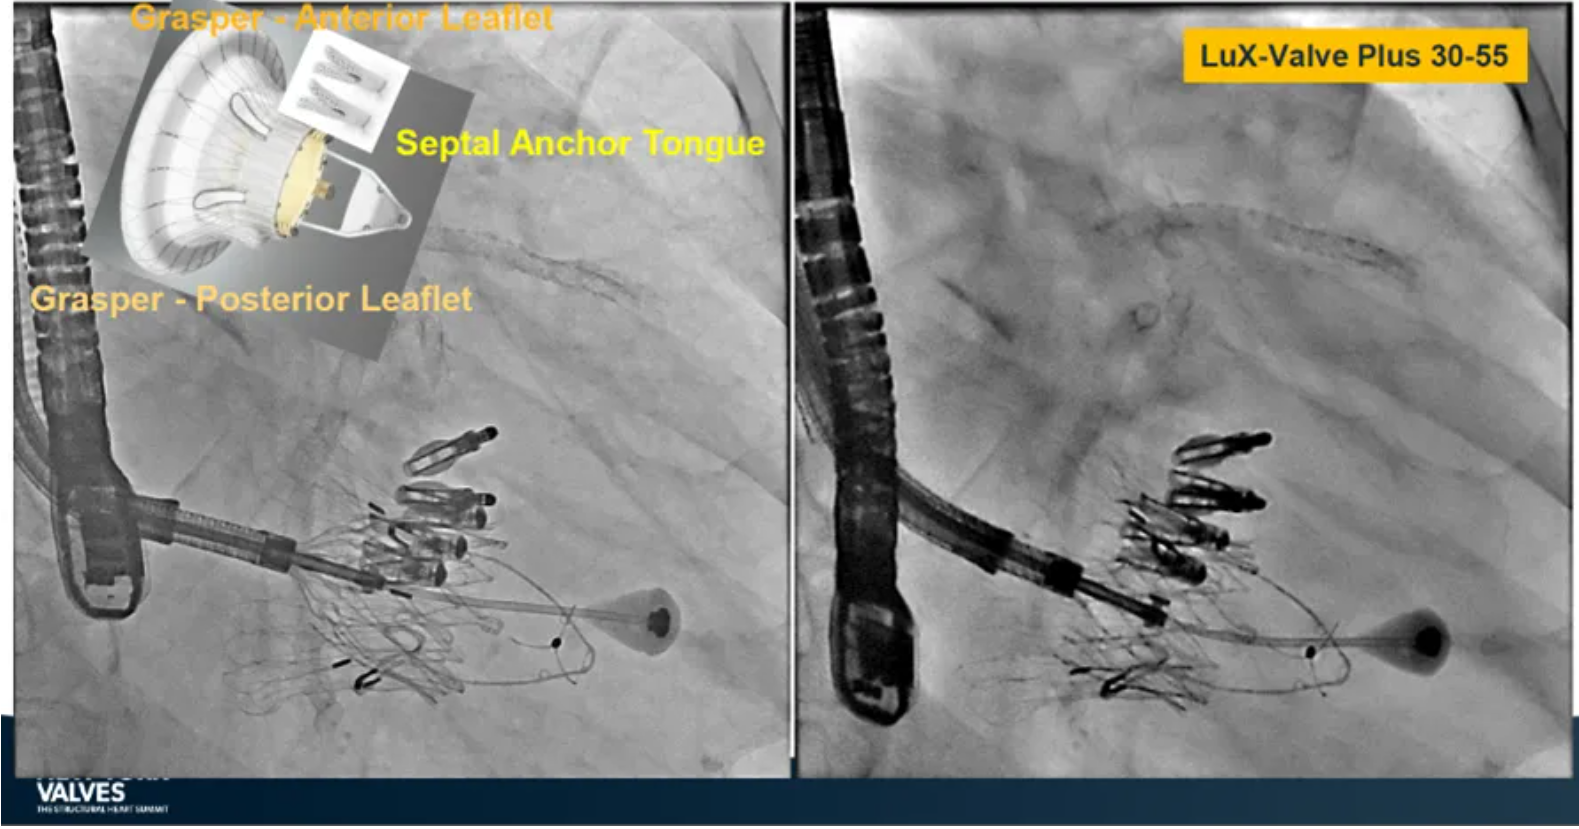

Granada教授表示,LuX-Valve Plus是一款不依賴于徑向支撐力固定的多功能TTVR器械,它的創(chuàng)新設(shè)計(jì)(室間隔錨定和瓣葉夾持件)提供了多樣的固定和穩(wěn)定技術(shù)。多中心臨床試驗(yàn)研究TRAVEL II 展現(xiàn)了LuX-Valve Plus的安全性和有效性,能實(shí)現(xiàn)較短的器械操作時(shí)間,較低的復(fù)合事件發(fā)生率,并在6個(gè)月期時(shí)顯著降低三尖瓣反流等級(jí),以及帶來(lái)心功能和生活質(zhì)量等指標(biāo)上的明顯改善。

來(lái)自法國(guó)波爾多大學(xué)醫(yī)院(CHU de Bordeaux, Bordeaux, France)的Thomas Modine教授在2024紐約瓣膜會(huì)上介紹到針對(duì)目前三尖瓣反流臨床上的痛點(diǎn),包括大瓣環(huán)、起搏器或者心臟除顫器ICD導(dǎo)線的影響、依賴術(shù)中影像,以及術(shù)后起搏器的植入等,LuX-Valve Plus都能夠提供良好的解決方案。他在最后總結(jié)道,LuX-Valve Plus創(chuàng)新的設(shè)計(jì)能夠有效降低術(shù)后的并發(fā)癥,例如起搏器植入率和血栓的形成。同時(shí),TRAVEL II 研究的6個(gè)月期數(shù)據(jù)也體現(xiàn)了產(chǎn)品較短的器械操作時(shí)間,較低的復(fù)合事件發(fā)生率,顯著改善的心功能和生活質(zhì)量,以及能夠跟術(shù)前就已經(jīng)存在的起搏器導(dǎo)線兼容的優(yōu)勢(shì)。

來(lái)自中國(guó)上海復(fù)旦大學(xué)附屬中山醫(yī)院的魏來(lái)教授在2024年臺(tái)北瓣膜高峰論壇上分享了他使用LuX-Valve Plus治療三尖瓣反流的經(jīng)驗(yàn)。魏來(lái)教授闡述道,隨著療法演變,目前全球市場(chǎng)有以LuX-Valve Plus及其他產(chǎn)品為代表的經(jīng)導(dǎo)管三尖瓣介入置換系統(tǒng),逐漸成為重度三尖瓣反流的一線治療方案。他介紹到,LuX-Valve Plus創(chuàng)新的室間隔錨定和經(jīng)頸靜脈入路的方式,能夠帶來(lái)安全穩(wěn)定的錨定效果及較短的輸送行程;其可調(diào)彎的輸送系統(tǒng)能保證同軸性,從而快速和安全地將人工瓣膜送達(dá)目標(biāo)手術(shù)區(qū)域,有效降低入路周邊解剖組織并發(fā)癥及術(shù)中出血風(fēng)險(xiǎn)。